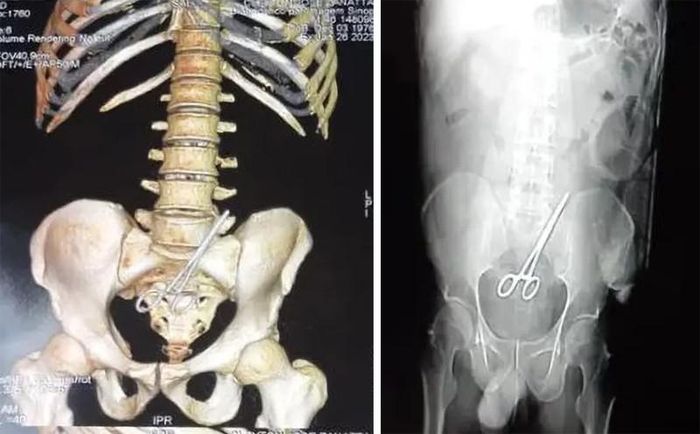

Ngày 20/1, ông Cleyton Jose Zanatta, Ủy viên hội đồng thành phố Nova Santa Helena ở bang Mato Grosso (Brazil), tới một bệnh viện gần đó để cắt bỏ khối u trong ruột.

Tuy nhiên, vị chính trị gia cảm thấy có điều gì đó không ổn khi ốm mệt suốt 6 ngày sau ca phẫu thuật. Thành viên Đảng Dân chủ Xã hội Brazil đã trở lại bệnh viện trên để kiểm tra.

Theo New York Post, kết quả chụp CT ghi nhận, trong bụng của ông Zanatta có một chiếc kéo. Báo cáo cho biết các bác sĩ đã để quên dụng cụ cắt chỉ bên trong người bệnh nhân khi khâu vết thương cho ông. Sau đó, ê-kíp phẫu thuật lấy chiếc kéo ra khỏi bụng của ông Zanatta. Người bệnh đã bình phục sau sự cố y tế và đang trong tình trạng ổn định.